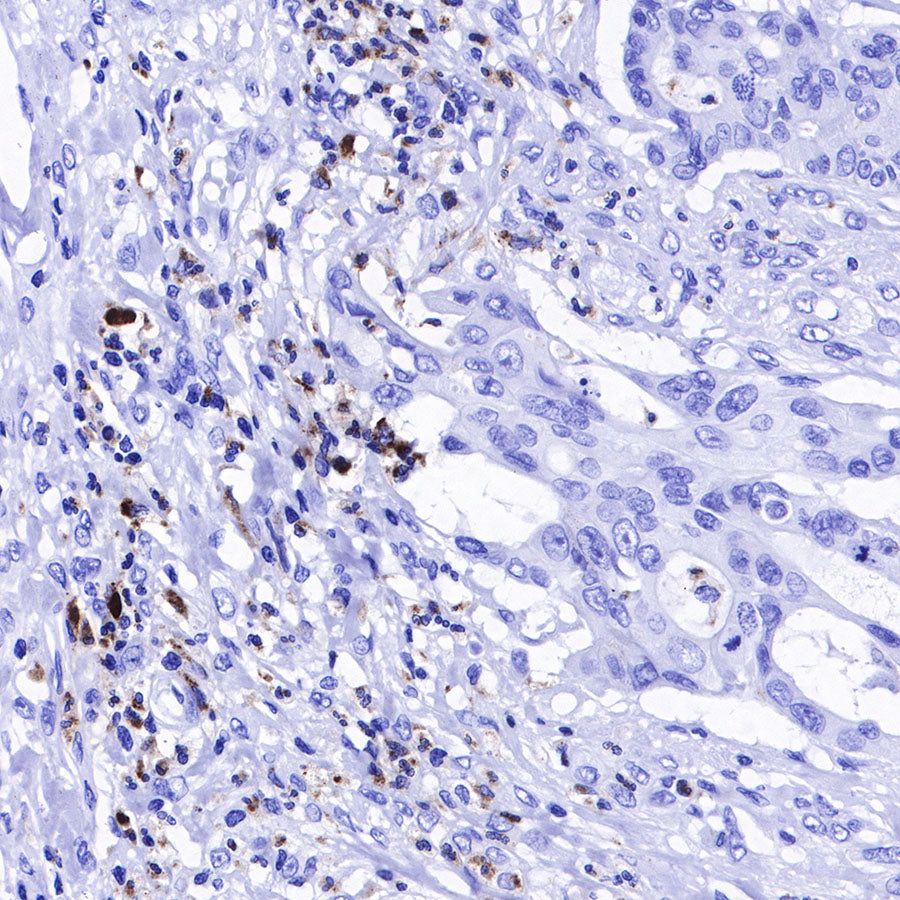

IHC shows positive staining in paraffin-embedded human liver. Anti-Lysozyme antibody was used at 1/100 dilution, followed by a HRP Polymer for Mouse & Rabbit IgG (ready to use). Counterstained with hematoxylin. Heat mediated antigen retrieval with Tris/EDTA buffer pH9.0 was performed before commencing with IHC staining protocol.

IHC shows positive staining in paraffin-embedded human tonsil. Anti-Lysozyme antibody was used at 1/100 dilution, followed by a HRP Polymer for Mouse & Rabbit IgG (ready to use). Counterstained with hematoxylin. Heat mediated antigen retrieval with Tris/EDTA buffer pH9.0 was performed before commencing with IHC staining protocol.

IHC shows positive staining in paraffin-embedded human spleen. Anti-Lysozyme antibody was used at 1/100 dilution, followed by a HRP Polymer for Mouse & Rabbit IgG (ready to use). Counterstained with hematoxylin. Heat mediated antigen retrieval with Tris/EDTA buffer pH9.0 was performed before commencing with IHC staining protocol.

IHC shows positive staining in paraffin-embedded human colon cancer. Anti-Lysozyme antibody was used at 1/100 dilution, followed by a HRP Polymer for Mouse & Rabbit IgG (ready to use). Counterstained with hematoxylin. Heat mediated antigen retrieval with Tris/EDTA buffer pH9.0 was performed before commencing with IHC staining protocol.

IHC shows positive staining in paraffin-embedded human ovarian cancer. Anti-Lysozyme antibody was used at 1/100 dilution, followed by a HRP Polymer for Mouse & Rabbit IgG (ready to use). Counterstained with hematoxylin. Heat mediated antigen retrieval with Tris/EDTA buffer pH9.0 was performed before commencing with IHC staining protocol.

IHC shows positive staining in paraffin-embedded human lung squamous cell carcinoma. Anti-Lysozyme antibody was used at 1/100 dilution, followed by a HRP Polymer for Mouse & Rabbit IgG (ready to use). Counterstained with hematoxylin. Heat mediated antigen retrieval with Tris/EDTA buffer pH9.0 was performed before commencing with IHC staining protocol.

IHC shows positive staining in paraffin-embedded human endometrial carcinoma. Anti-Lysozyme antibody was used at 1/100 dilution, followed by a HRP Polymer for Mouse & Rabbit IgG (ready to use). Counterstained with hematoxylin. Heat mediated antigen retrieval with Tris/EDTA buffer pH9.0 was performed before commencing with IHC staining protocol.